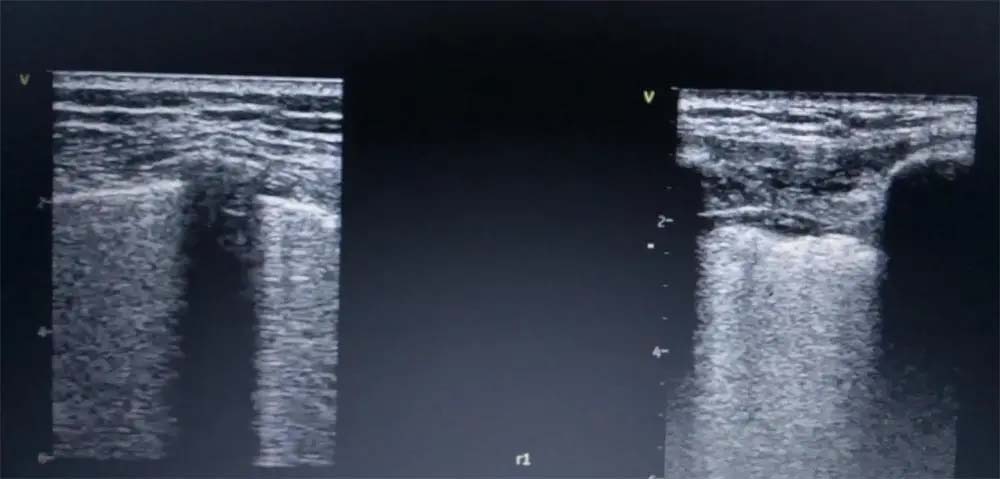

-Примената на ехото на бели дробови е голема со предност немање на радијација за разлика од КТ и рентгенграфијата. При различни дифузни заболувања како саркоидоза, реуматоиден артритис, СЛЕ, амилоидоза често се засегнати и белите дробови пришто ехографски се прикажуваат патолошки “Б“ линии.

Хиперехогените вертикални кои при белодробна конгестија се подвижни и почнуваат од глатка подвижна плеврална линија за разлика од дифузните белодробни заболувања кај кои има задебелување и ирегуларност на плевралната линија со хиперехогени вертикални линии и нивна слаба подвижност.